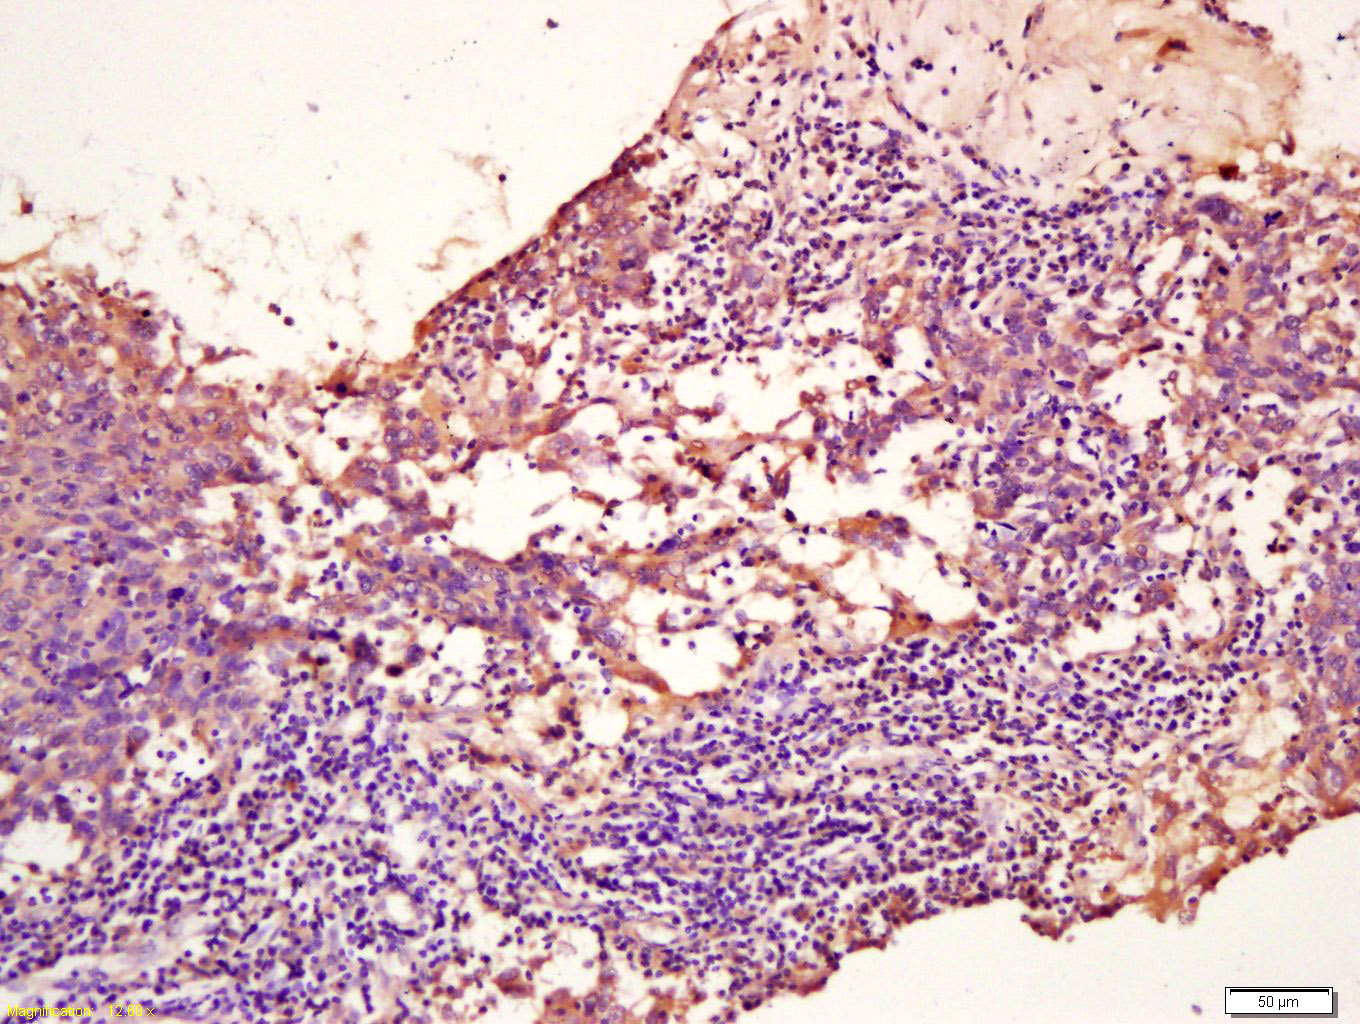

Tissue/cell: mouse stomach wall; 4% Paraformaldehyde-fixed and paraffin-embedded; Antigen retrieval: citrate buffer ( 0.01M, pH 6.0 ), Boiling bathing for 15min; Block endogenous peroxidase by 3% Hydrogen peroxide for 30min; Blocking buffer (normal goat serum,C-0005) at 37℃ for 20 min; Incubation: Anti-TPM2 Polyclonal Antibody, Unconjugated(bs-1243R) 1:200, overnight at 4°C, followed by conjugation to the secondary antibody(SP-0023) and DAB(C-0010) staining

Tissue/cell: human breast carcinoma; 4% Paraformaldehyde-fixed and paraffin-embedded; Antigen retrieval: citrate buffer ( 0.01M, pH 6.0 ), Boiling bathing for 15min; Block endogenous peroxidase by 3% Hydrogen peroxide for 30min; Blocking buffer (normal goat serum,C-0005) at 37℃ for 20 min; Incubation: Anti-TPM2 Polyclonal Antibody, Unconjugated(bs-1243R) 1:200, overnight at 4°C, followed by conjugation to the secondary antibody(SP-0023) and DAB(C-0010) staining